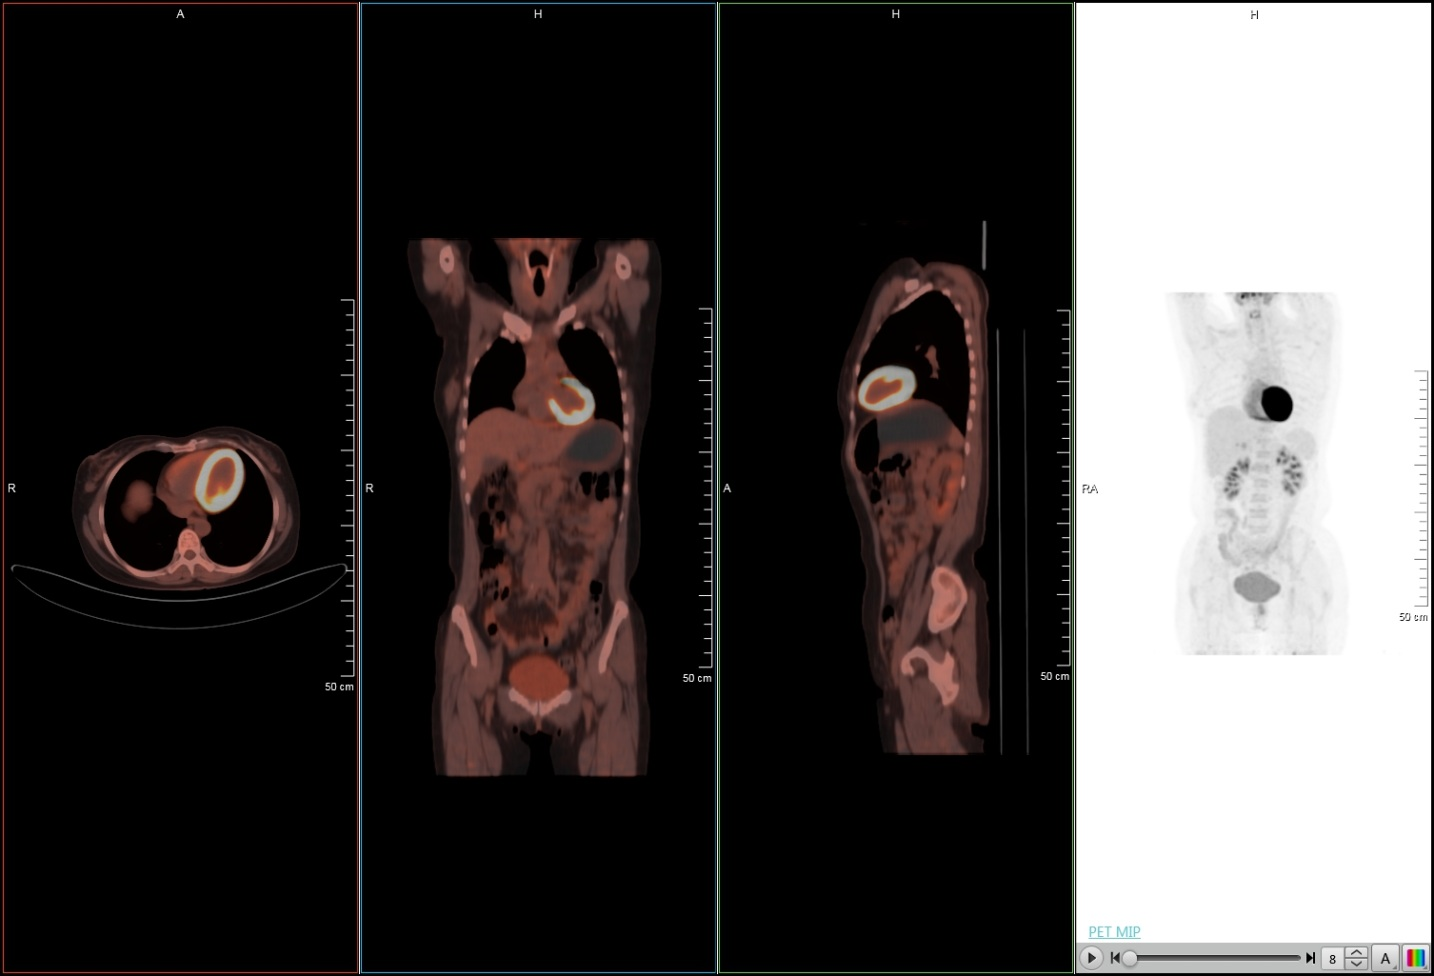

下面的临床图像展示了uMI 510光导PET-CT的优异性能:

超清PET图像

脑部图像

心脏成像

大体重病人低剂量

以下是中山医院两台PET-CT设备临床图像对比:

淋巴瘤治疗后随访病例

同一时间不同设备对比显示淋巴结

通过两台设备临床图像的对比分析可看出,联影PET-CT图像分辨率更高,对比度更优,能更好的满足临床科室的需求。